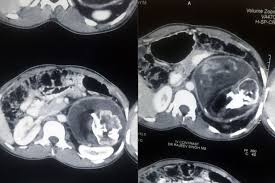

Siapa kata sakit perut tidak serius. Jika ada simptom lain tidak normal, seperti sakit bahagian pinggang yang kerap dan berpanjangan. Sakit perut tanpa sebab klinikal. Kenali 11 simptom kanser perut yang mungkin terlepas pandang. Mashita nasihat untuk saya buat pembedahan segera. Salah satu bentuk rasa sakit yang dikeluhkan selain kram adalah perut melilit. Sakit perut dibahagikan kepada dua iaitu akut dan kronik. Keputusan terus dibuat dan rabu pagi saya dibedah selama 4 jam 30 minit. Maka, hal tersebut dapat menyebabkan rasa sakit pada perut bagian bawah seusai melakukan seks. Salah satu simptomnya ialah sakit perut berpanjangan. You can download free mp3 as a separate song and download a music collection from any artist, which of course will save you a. Nampaknya kena pergi farmasi sekejap lagi ni. Beberapa keluhan sakit perut yang berhubungan dengan kelelahan, sembelit, salah makan atau akibat demam bisa diobati dengan jahe.

Sakit Perut Berpanjangan Tanda Kanser Perut Semak 11 Simptom Ini

Sakit Perut Berpanjangan Tanda Kanser Perut Semak 11 Simptom Ini from cdn.hellodoktor.com